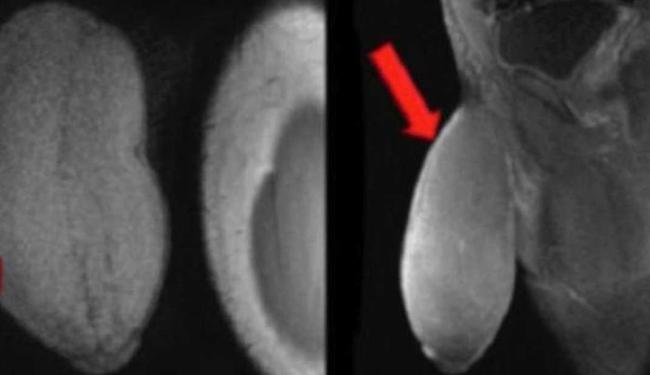

O órgão do rapaz era muito largo (25 cm de circunferência) e tinha quase 18 cm de comprimento, em estado flácido. O adolescente sofria priapismo – condição em que pênis fica ereto mesmo em momento de não excitação.

O médico, junto com sua equipe, estudou o caso sobre a redução e, após pesquisas, o especialista desenvolveu uma técnica para atender a solicitação do paciente.